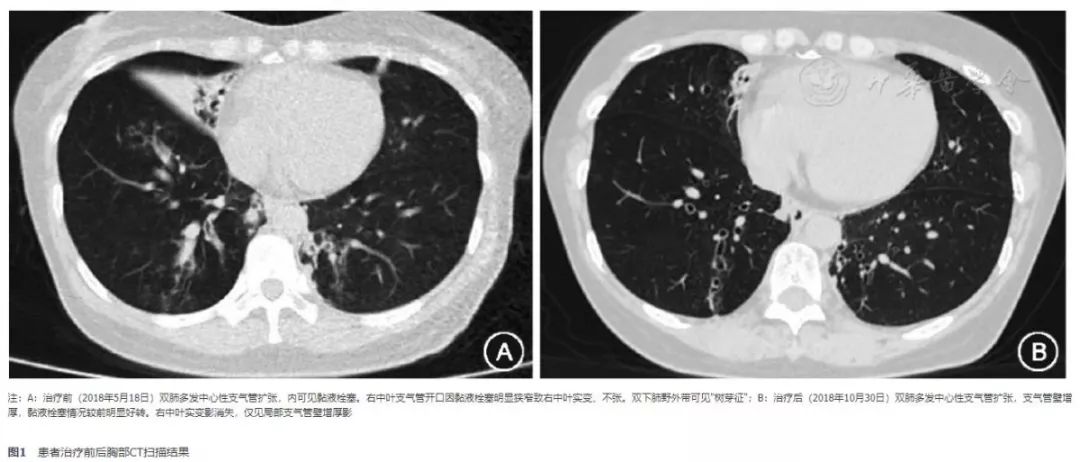

患者女,54岁,因"反复咳嗽、喘息12年,加重6年"于2018年5月28日入住中日友好医院。患者12年前出现发作性咳嗽、喘息,遇冷空气、烟尘等可诱发加重。6年前症状发作频繁,于外院就诊。查体双肺可闻及散在呼气末哮鸣音;胸部CT示"双肺支气管扩张伴感染",血清总IgE"752 U/ml",烟曲霉特异性IgE"阳性",肺功能示"阻塞性通气功能障碍",呼出气一氧化氮(FeNO)体积浓度为35 ppb(1 ppb=1×10-9),诊断为"变应性支气管肺曲霉菌病(ABPA)"。给予醋酸泼尼松(20 mg 1次/d口服,每4周减5 mg,直至减停)及伊曲康唑口服液(200 mg 2次/d口服)治疗,症状明显好转。药物减停后症状复发,多次就诊当地医院予静脉激素治疗。近半年反复咳嗽、喘息伴肺部渗出影。为求进一步诊治入住我科。既往过敏性鼻炎、鼻窦炎伴嗅觉减退14年。分泌型中耳炎伴听力减退6年;对多种食物、药物过敏。入院体检:消瘦体型(体质指数18.37 kg/m2),嗅觉减退、听力下降。双肺散在呼气相哮鸣音。哮喘控制测试(ACT)评分15分。辅助检查:外周血嗜酸细胞计数:1.99×109/L。血清总IgE:737 U/ml。烟曲霉特异性IgE:2.48 kUA/L(2级)。自身抗体谱及血管炎抗体谱均未见明显异常,其余常规化验均正常。肌电图"未见明显神经源性损害"。胸部CT(2018年5月18日)示双肺多发中心性支气管扩张,内可见黏液栓塞。右中叶支气管开口因黏液栓塞明显狭窄致右中叶实变、不张。双下肺野外带可见"树芽征"(图1A)。鼻窦CT(2018年5月24日)示"全组副鼻窦炎"。肺功能检查示:第一秒用力呼气容积占预计值百分比(FEV1%预计值)为30.4%。FeNO体积浓度为55 ppb。支气管镜检查:右中叶及右下叶支气管黏膜水肿开口明显狭窄。支气管肺泡灌洗液及痰病原学均阴性。灌洗液嗜酸细胞79%。诱导痰嗜酸细胞56%。按照2013年国际人类和动物真菌学会(ISHAM)专家组提出的ABPA诊断标准[1],该患者虽然血清总IgE尚未达到1 000 U/ml,综合其临床特点应为ABPA早期阶段。遂于5月30日给予醋酸泼尼松20 mg 1次/d(2周减5 mg,减至5 mg时维持)口服联合伊曲康唑口服液200 mg 2次/d口服、沙美特罗替卡松(50 μg/250 μg)1吸2次/d治疗。同时给予孟鲁司特钠10 mg 1次/d口服及鼻喷激素治疗。该患者既往给予ABPA规范治疗症状仍反复发作,并抵触长期口服激素,故寻求更合适的治疗方法。根据文献资料,抗IgE单抗治疗IgE介导的过敏性疾病可临床获益[2,3],为此,根据患者血清总IgE水平及体重,予奥马珠单抗600 mg皮下注射1次/月治疗,计划使用16周后判断其有效性,若有效则持续规律应用。并嘱患者每日监测呼气峰流速(PEF)。10月30日复诊(醋酸泼尼松已减至5 mg 1次/d口服),患者咳嗽、喘息症状明显减轻,哮喘控制测试(ACT)评分24分,达到良好控制。听力及嗅觉明显改善。近4周的监测PEF值均在个人预计值的100%以上。外周血嗜酸细胞计数:0.99×109/L(较前明显降低)。血清总IgE:1 090 U/ml。肺功能检查示:FEV1%预计值为94.8%。FeNO体积浓度为88 ppb。10月30日复查胸部CT示"双肺多发中心性支气管扩张,支气管壁增厚,黏液栓塞情况较前明显好转。右中叶实变影消失,仅见局部支气管壁增厚"(图1B)。

图1 患者治疗前后胸部CT扫描结果